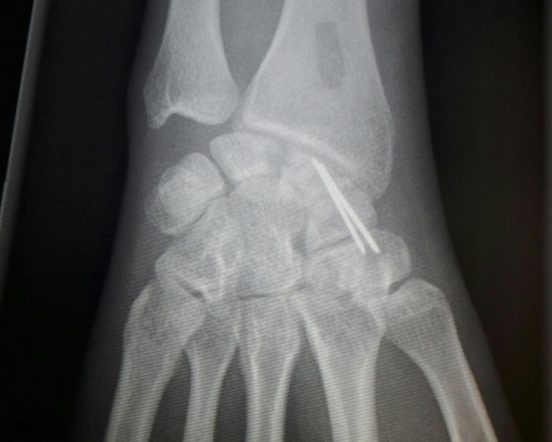

Fijación con injerto oseo y agujas de la fractura. Visión AP